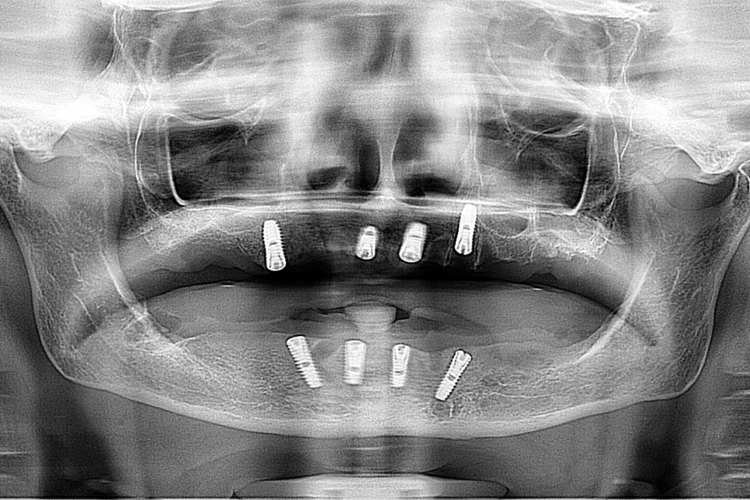

Pacienta in varsta de 75 ani, a pierdut dintii complet la ambele maxilare. Se prezinta in clinica si solicita proteze functionale fixe. Pentru refacerea arcadelor prin solutii implanto-protetice s-au inserat un numar mic de implante (4 implante superior si 4 inferior) care au fost folosite la constructia unei infrastructuri a protezelor, cu bara intre implante, capse laterale si suprastructura armata overdanture. Supraprotezele inserate pe bara satisfac estetica si functionalitatea ca o lucrare dentara fixa.